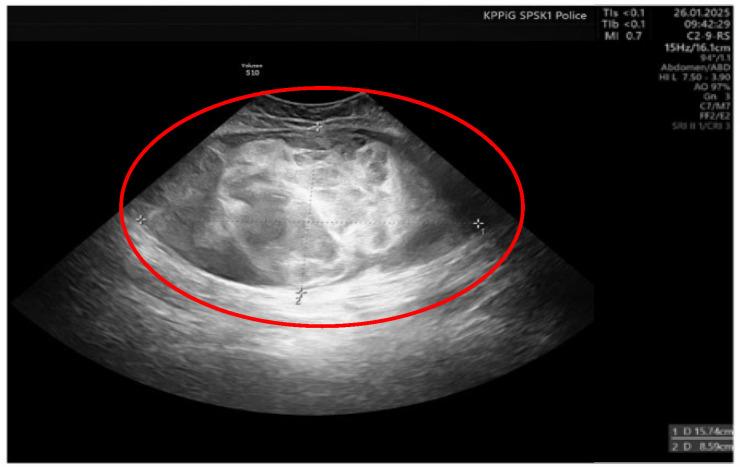

We report the case of a 36-year-old female patient on the 11th day of the puerperium after a cesarean section. The patient presented to the gynecology ward owing to the sudden appearance of a tumor in the medial part of her right thigh. The lesion was non-painful, mobile, soft, approximately 20 cm in diameter, and protruded above the level of the rest of the thigh surface. A suspicion of hematoma was raised. The final diagnosis was high-grade MLPS.